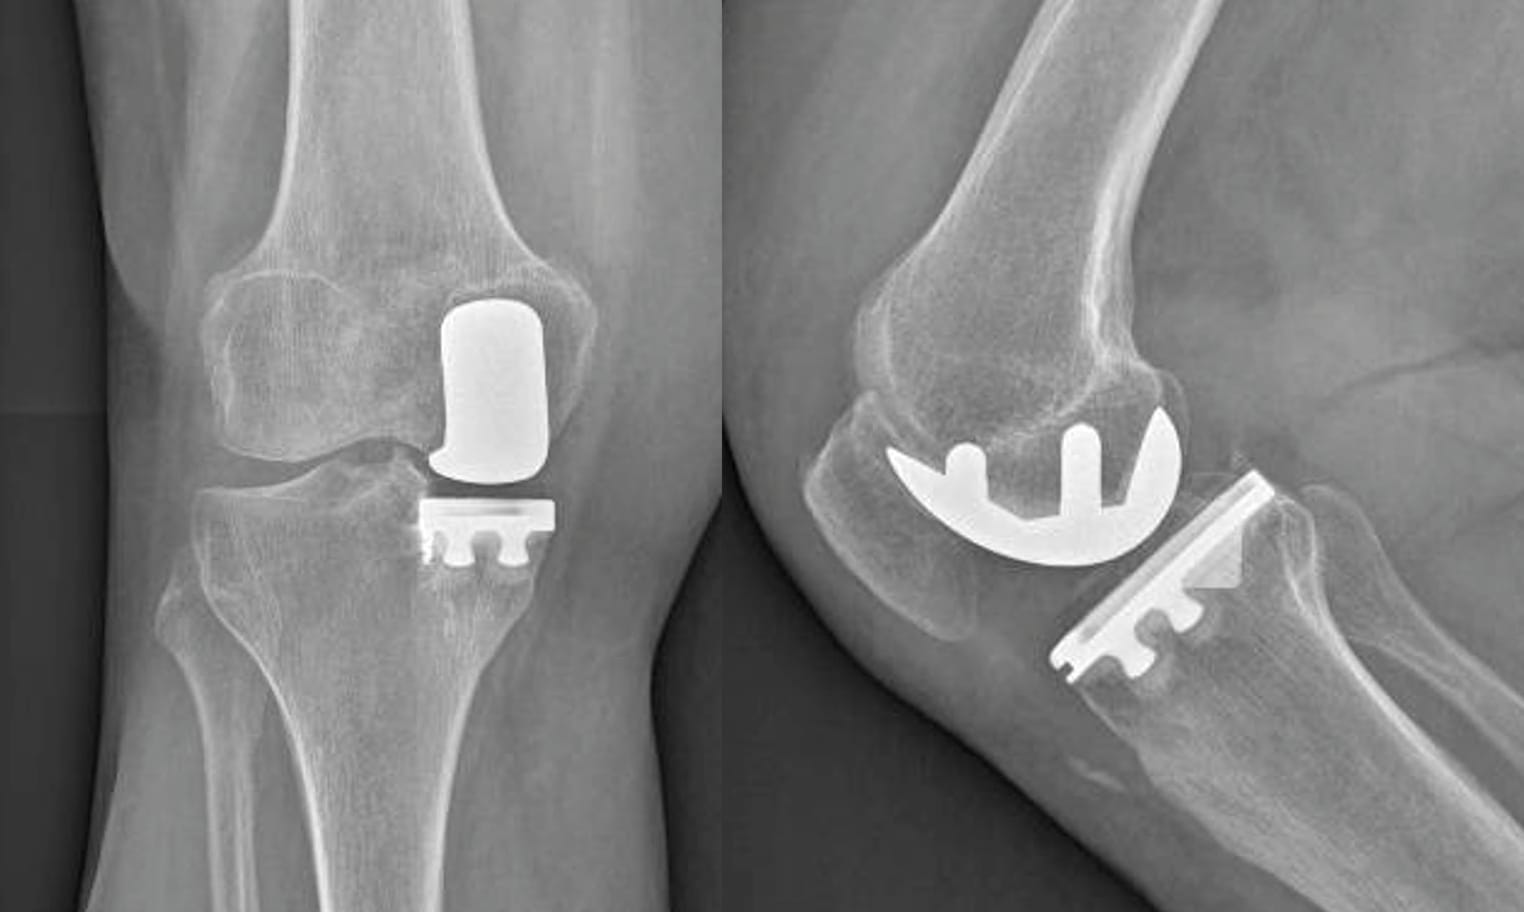

In terms of design and kinematics, medial UKA can be categorized into two main groups: fixed-bearing and mobile-bearing implants. Mobile bearing UKA features a congruent yet mobile polyethylene insert atop a polished tibial component, while fixed-bearing designs comprise an anatomic femoral component paired with a flat polyethylene insert, either noncongruent and affixed to the tibial baseplate (metal back) or directly cemented onto the bone (referred to as all Poly) (Figure 1). Extensive research has demonstrated excellent functional recovery for both designs, with no statistically significant difference in revision rates but variations in the modes and timing of failures.